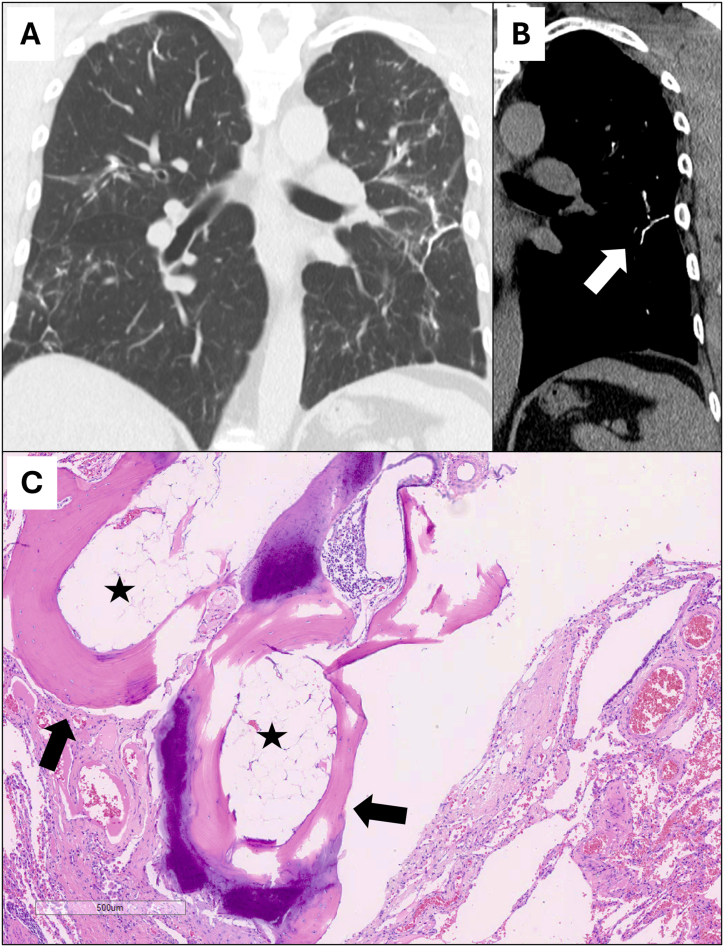

Dendriform pulmonary ossification (DPO) is a rare condition characterized by mature bone formation in the lung. DPO has been linked to various conditions, but little is known about the link between DPO and hazardous airborne exposures. We queried research databases of military personnel evaluated for deployment-related respiratory diseases at two occupational pulmonary medicine clinics (Colorado, USA) for diagnoses of DPO, and summarized demographics, Gulf War military deployment history, medical history, and pulmonary function testing. Chest imaging was independently reviewed and scored by a thoracic radiologist, and all cases had undergone lung tissue biopsy. We identified five male combat veterans with DPO, median age 49 years [range: 32–64]. All had deployed to Southwest Asia or Afghanistan during the First or Second Gulf War, and all reported frequent, intense exposure to diesel exhaust, burn pit emissions, and sandstorms. Lung physiology was abnormal in all cases. The most prevalent chest imaging and histopathology findings were airway-centric injury, inflammation, and retained particulate matter, suggesting substantial hazardous exposure during military deployment. This case series of a rare lung disease from the only two contemporary Colorado clinics serving previously deployed veterans highlights a potential link between airborne hazards and lung injury leading to DPO. A high index of clinical suspicion combined with a detailed occupational history may reveal additional exposure-related associations with DPO. Access to large medical databases of military veterans with linkage to exposure histories may further elucidate risk factors for lung injury with ossification, paving the way for targeted prevention.